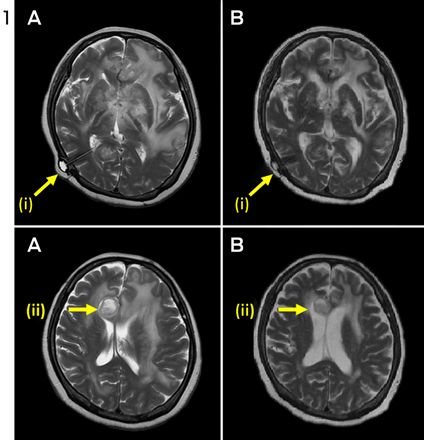

A 60-year-old HIV-negative woman presented with a week's history of fever, vomiting and confusion, followed by progressive personality change. On admission, she was noted to have urinary retention, left oculomotor nerve palsy and an upgoing right plantar response. A magnetic resonance image (MRI) of the brain showed leptomeningeal enhancement with gyral swelling and subtle cortical T2 signal hyperintensity in the right frontal lobe, suggesting meningoencephalitis. Cerebrospinal fluid (CSF) cultures grew fully susceptible Mycobacterium tuberculosis. Antituberculous therapy was started with isoniazid, rifampicin, ethambutol and pyrazinamide, plus dexamethasone. CSF cultures tested negative by Week 1. Over the next month, she had ongoing fevers and fluctuating conscious state. High CSF pressures necessitated ventriculoperitoneal (VP) shunting. An MRI 3 months into therapy showed numerous granulomas, microabscesses and infarcts. Her condition failed to improve with a further course of dexamethasone, and an MRI at 5 months showed increasing size and number of granulomas, with worsening oedema and midline shift (Figure 1, A). She was given a trial of three doses of infliximab 10 mg/kg, 1 month apart, resulting in marked improvement in neurological status and radiological findings (Figure 1, B). She regained movement of her limbs, opened her eyes spontaneously and was able to articulate a few words. After completing 2 months of four-drug therapy, she received isoniazid and rifampicin for 10 months, with ongoing improvement. She was left with mild cognitive deficit and required some assistance with activities of daily living.